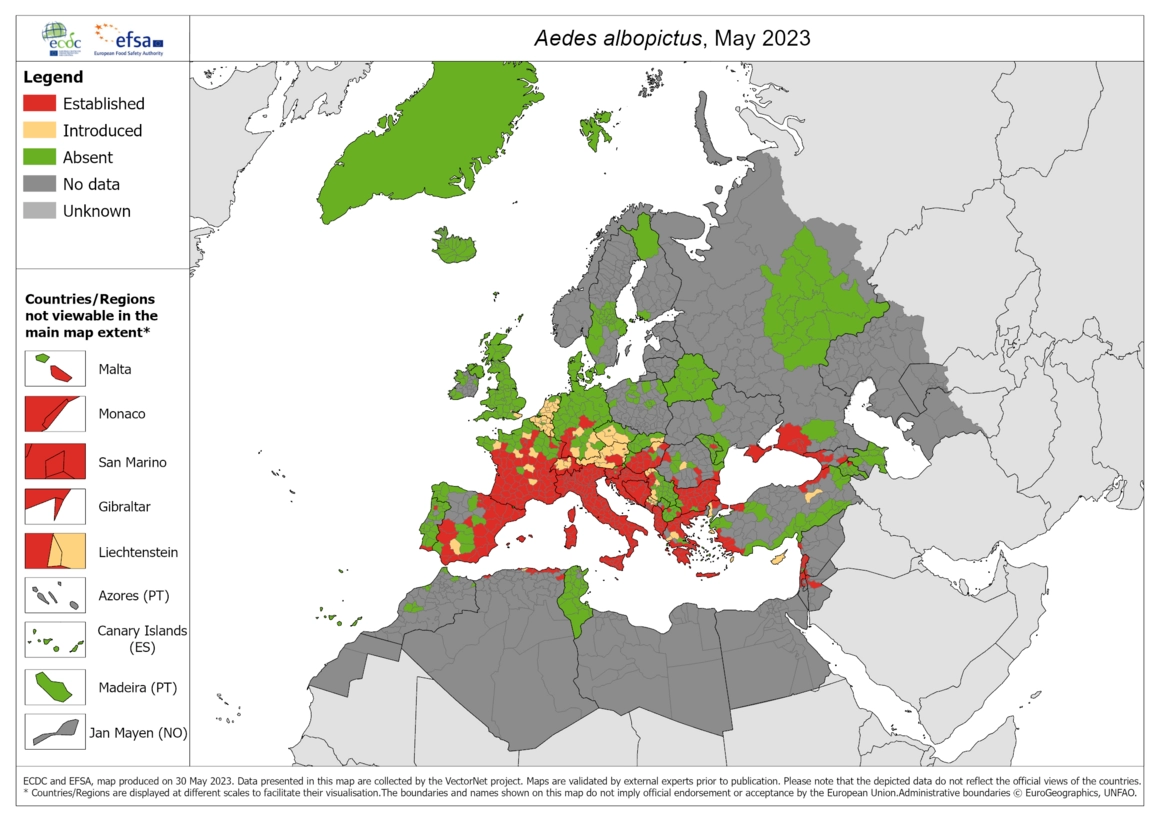

基孔肯雅熱是一種由基孔肯雅病毒引起的疾病,主要透過蚊子叮咬傳播。這種病毒主要由埃及斑蚊(Aedes aegypti)和白線斑蚊(Aedes albopictus)傳播,牠們在熱帶和亞熱帶地區活動頻繁。當帶病毒的蚊子叮咬人類時,病毒就會進入體內,導致感染。

這波爆發與季節性氣候有密切關係。春夏交替時期氣溫回升,濕度增加,為帶有病毒的埃及斑蚊(Aedes aegypti)及白紋伊蚊(Aedes albopictus)繁殖提供理想環境。積水處增多亦促進蚊群數量上升,病毒傳播風險隨之提升。此外,人流集中和戶外活動增多,加快了病毒在人群間傳播。

基孔肯雅熱主要透過帶有病毒的蚊子叮咬傳播,最常見的兩種蚊子是埃及斑蚊(Aedes aegypti)和白線斑蚊(Aedes albopictus)。這兩種蚊子白天活躍,特別喜歡在人類周圍繁殖和叮咬。